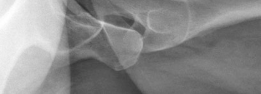

With the trochanter flipped, the superior, anterior, and posterior aspects of the hip capsule are exposed. To protect the retinacular vessels, which run along the posterosuperior neck, the capsulotomy must be performed with extreme care. A Z-shaped capsulotomy is standard for the right hip (reverse Z for the left). The longitudinal limb is made along the anterosuperior axis of the femoral neck, staying well away from the posterosuperior retinacular vessels. The proximal limb runs along the acetabular rim, and the distal limb runs inferiorly. Heavy sutures are placed in the capsular flaps for later repair.

Dislocation of the femoral head is achieved by flexion, adduction, and external rotation of the leg. The ligamentum teres, if intact, is sharply transected using specialized curved scissors. Once dislocated, the femoral head and acetabulum are inspected. In our index case, significant anterolateral cartilage loss and an absent labrum are encountered. The acetabular rim is prepared, and a labral reconstruction is performed. An allograft (e.g., semitendinosus) or autograft (iliotibial band) is tubularized and secured to the acetabular rim using multiple knotless suture anchors. This restores the critical fluid seal and anterior bumper. Concurrently, any abnormal CAM morphology on the femoral head-neck junction is addressed via osteochondroplasty using high-speed burrs and curved osteotomes, ensuring spherical congruence.